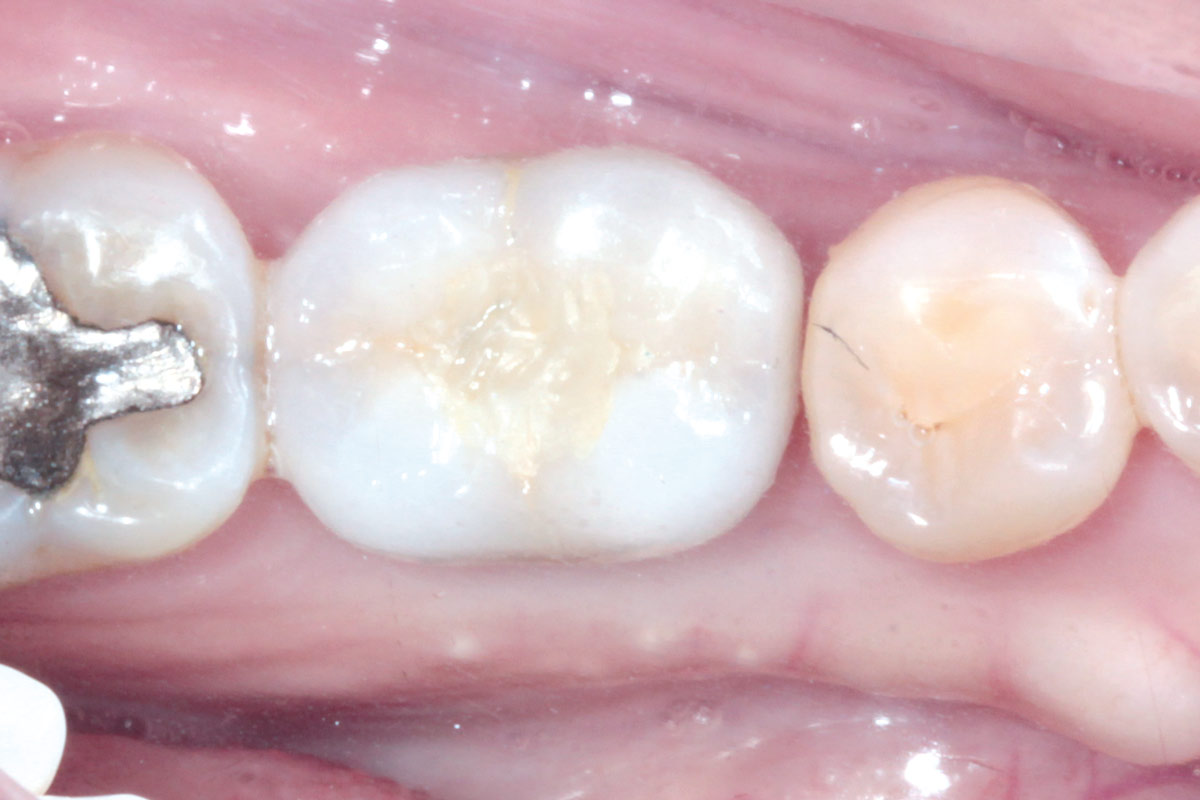

4/19 - Initial clinical situation before extraction and implantation

Immediate implant placement using maxresorb® - Dr. Alejandro Signorio